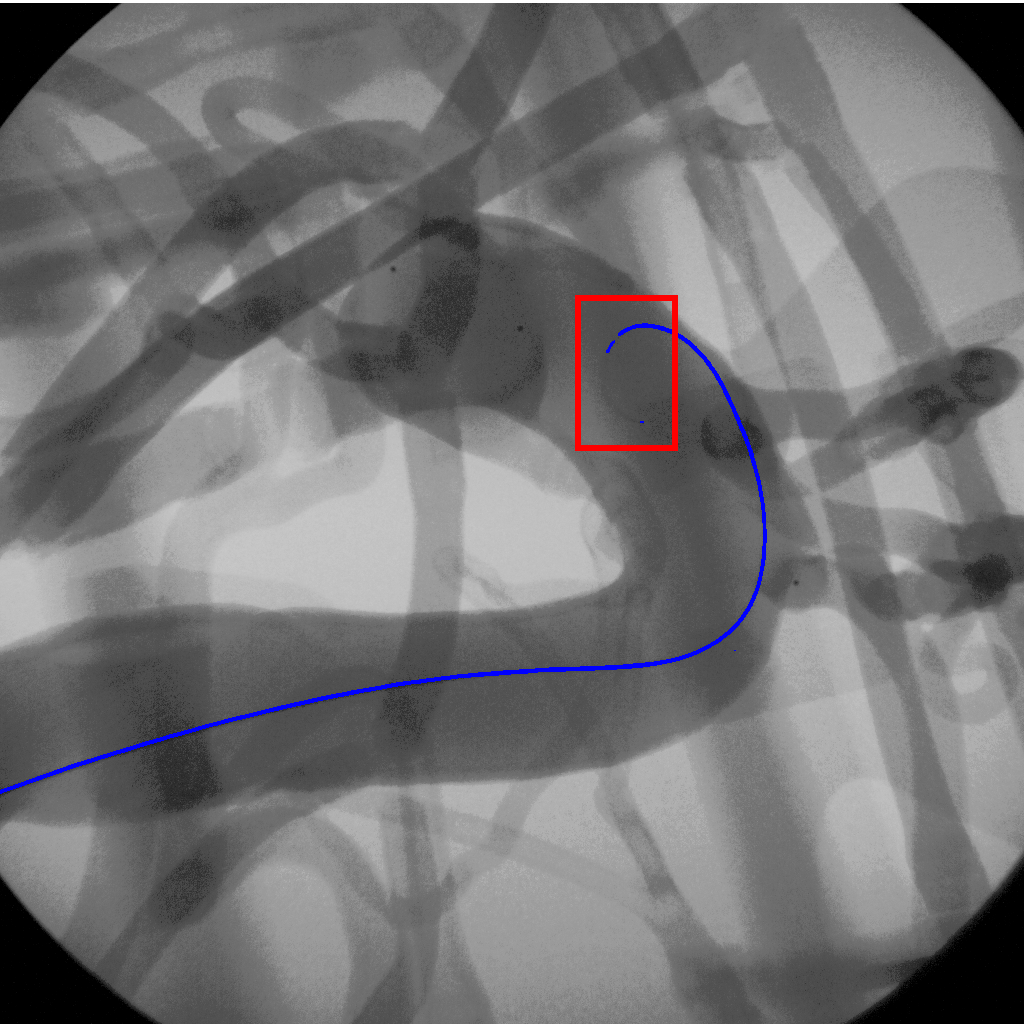

Recent advancements in deep learning, have introduced more robust approaches for guidewire segmentation. Convolutional Neural Networks (CNNs) have shown notable improvements by automatically extracting features from medical images [34, 35, 36, 37, 38, 39]. Research in this area spans from segmenting the tip, to a dual segmentation of guidewires and catheters [38]. Architectures like U-Net [40] have achieved state-of-the-art results in segmentation tasks, and further refinements such as adaptive U-Net and scale-recurrent networks have improved performance in X-ray image sequences [41, 42]. Despite these advancements, deep learning models face challenges often struggle to represent the continuous geometry of the guidewires, leading to suboptimal clinical results. The most common form of failure cases is represented by surgical tool fragmentation, as highlighted in numerous studies [43, 44, 45] and which can be visualized in Fig. 2. This highlights the need for methods capable of preserving the inherent smoothness of the tools while maintaining segmentation accuracy across varying conditions.

We trained our network, SplineFormer, on the annotated dataset described in Section III. The model was trained for 300 epochs using the Adam optimizer with an initial learning rate of . The results, presented in Fig. 7, illustrate that SplineFormer successfully predicts the overall shape of the guidewire within a compressed feature space. While SplineFormer is not explicitly designed for segmentation, it demonstrates a strong ability to detect key points of the guidewire, particularly near the tip. In contrast, traditional segmentation models such as U-Net [40] generate qualitative masks but fail to capture the guidewire’s detailed geometry, often missing the tip due to low contrast. Consequently, U-Net’s segmentation outputs tend to be discontinuous and provide insufficient visual guidance for stable autonomous endovascular navigation.